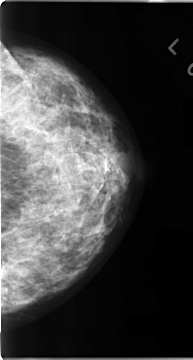

C_0098_1.LEFT_CC

LEFT_CC LINES 4680 PIXELS_PER_LINE 2504 BITS_PER_PIXEL 12 RESOLUTION 50 NON_OVERLAY